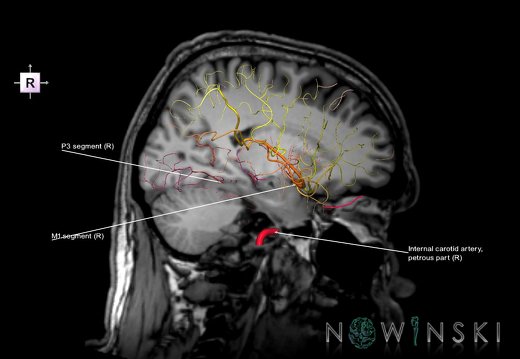

G6.T15.2.V2.P10.Intracranial arteries–Triplanar

G6.T15.2.V2.P10S.Intracranial arteries–Triplanar